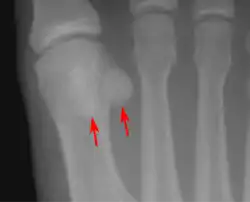

![]() العظام السمسمية عند الطرف البعيد لعظم مشط القدم الأول في القدم البشرية. العظام السمسمية عند الطرف البعيد لعظم مشط القدم الأول في القدم البشرية. | |